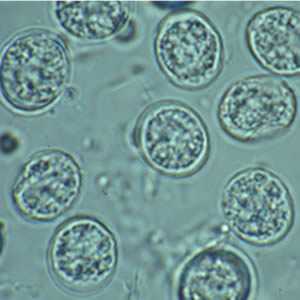

Toxoplasma gondii unsporulated oocysts.

Figure A: Unsporulated T. gondii oocyst in an unstained wet mount.

Figure B: Unsporulated oocyst of T. gondii in an unstained wet mount, viewed with differential interference contrast (DIC) microscopy.

Figure C: T. gondii oocysts in a fecal floatation.

Figure D: Higher magnification of Figure C.